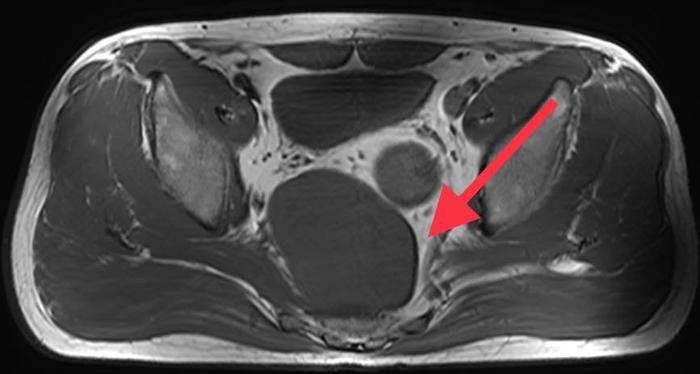

近日,余先生行色匆匆地来到同济大学附属东方医院胃肠肛肠外科傅传刚教授特需就诊,他自述自己既没有排便习惯的改变,身体也没有其它不舒服,但就是10天前在外院做B超检查时发现盆腔低回声,此外MR检查提示骶前直肠后可见一等T1,混T2回声,大小50*72*91mm肿物,结肠镜提示可见腔外压迫。余先生为此感到焦虑,难道自己得的是癌症?还是什么其他的疾病?他思虑万千,恳求傅传刚教授一定要帮他查出自己到底患了什么疾病!

傅传刚教授给余先生安排进行了详细查体和辅助检测。查体发现肛门外形正常,直肠指诊后壁齿线上约3cm向上可触及巨大肿物下缘,粘膜完整。盆腔(MRI增强)显示盆底占位,考虑神经源性肿瘤可能。

傅传刚教授结合余先生的病史、症状、体征、MR等,诊断明确,傅传刚教授和周主青教授于2020.09.14共同实施腹腔镜骶前肿瘤切除术

麻醉成功后,取截石位,常规消毒铺巾。经脐孔上切口置入12mm Trocar 1只导入腹腔镜,下腹部广泛粘连。骶前肿瘤约12*10*10cm。边界清楚,质韧,远端后壁与骶前筋膜粘连。探查见肝脏、脾脏等其他脏器未及明显异常。于左右锁骨中线处脐水平、左右下腹部各做小切口,置入5mm Trocar 3只,右下腹切口置入12mm Trocar一只。超声刀分解粘连,超声刀游离阑尾系膜至根部,距离根部0.5cm切断结扎阑尾并离断,取出标本,残端荷包包埋。切开乙状结肠右侧系膜,分离结肠后间隙,锐性切开直肠右侧系膜向下分离至肛提肌,显露两侧输尿管,并予以保护,避免损伤。沿直肠后间隙锐性向下分离直肠系膜至肛提肌处。显露肿块,沿肿块包膜解剖分离肿块周围间隙,显露并保护双侧腹下神经。终于,历经3个多小时,傅传刚教授将整个大的囊肿成功连根拔除。